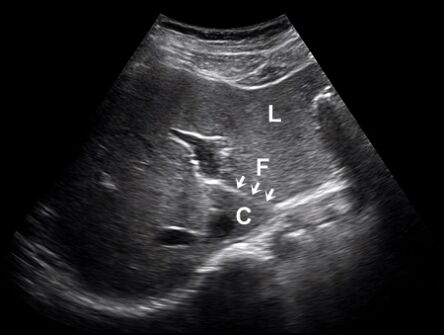

61.肝臟超音波橫向掃描時,在外側節段(lateral segment, L)與尾葉(caudate lobe, C)之間有 一高回音裂隙(fissure, F),如下圖箭號處。此高回音裂隙與下列何者最有關係? (A)靜脈韌帶(ligamentum venosum) (B)動脈韌帶(ligamentum arteriosum) (C)圓韌帶(ligamentum teres) (D)鎌狀韌帶(falciform ligament)